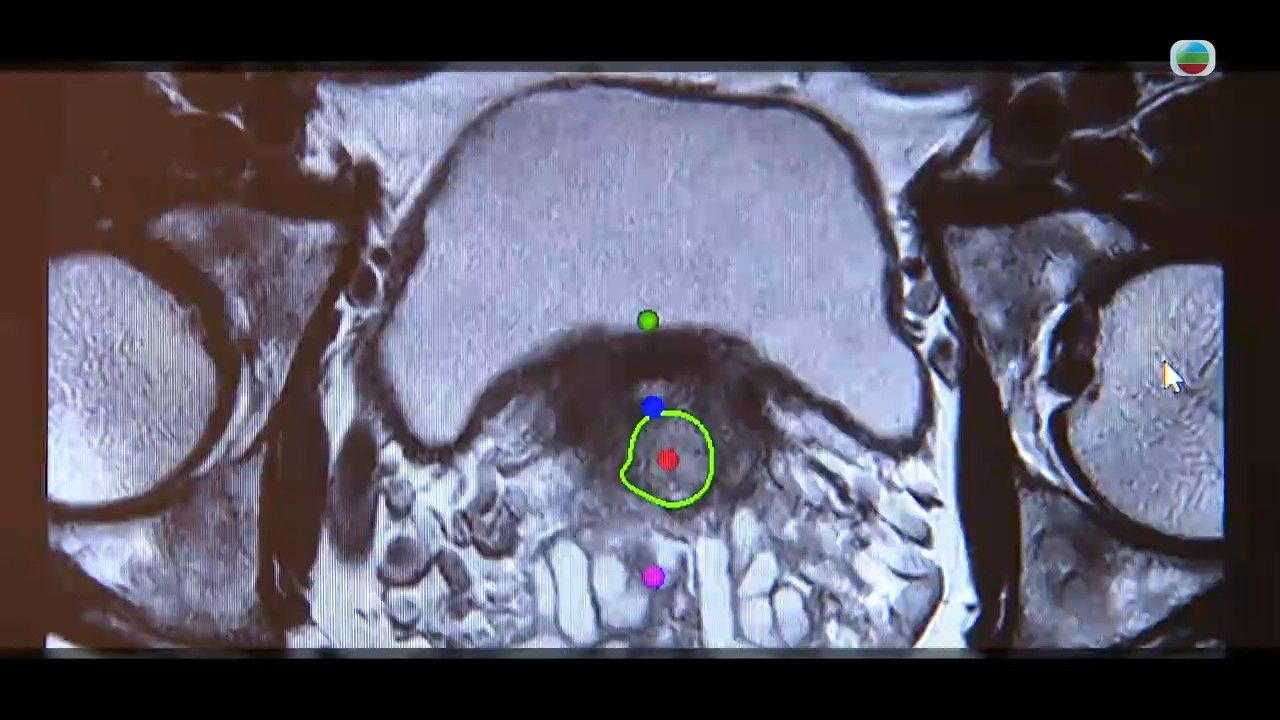

醫生建議,男士於50歲之後要定期抽血檢測前列腺癌風險,以提高存活率以及降低復發率。如果發現男士前列腺癌指數高,就會建議做磁力共振,有陰影就前列腺活組織檢查。